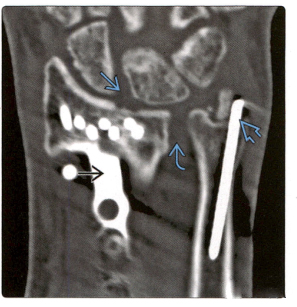

3.(Снимок слева) Задне-передняя рентгенограмма, сделанная сразу после репозиции перелома, показывает, что четыре спицы К пронизывают шиловидный отросток лучевой кости, а фрагменты перелома близки к анатомической репозиции. Дополнительная внешняя фиксация, вспомогательная фиксация.

(Фото справа) Заднепередняя рентгенограмма того же пациента через 2 недели показала смещение спицы К и неспособность редукции перелома, 2 спицы К пролапсировались, а 2 спицы К были смещены проксимально.